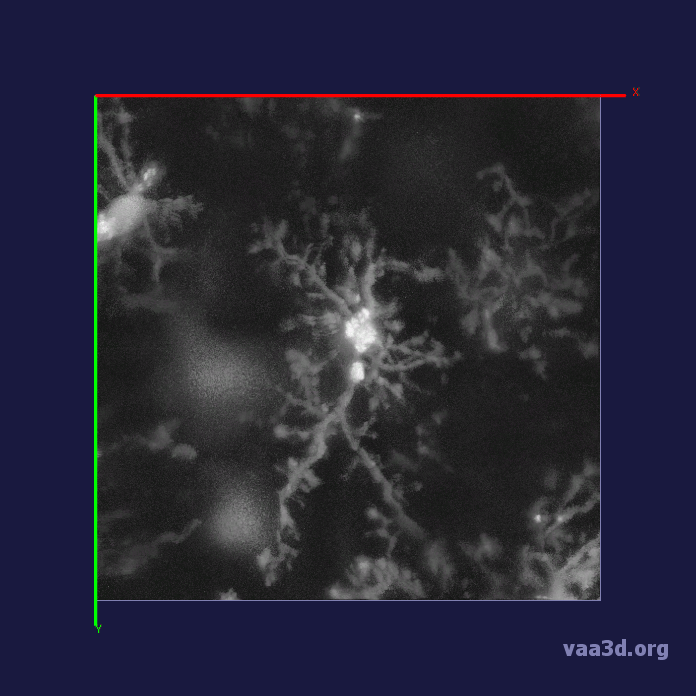

In our experiments, we compare the coupled TuFF-BFF microglia segmentation results with those given by L2S [21] and the Chan-Vese segmentation method [22]. The groundtruth in 3D was attained by manually tracing the object slice by slice from the z-stack. It must be noted that this was done by eye and could have some error. Figure 2 shows the visual comparison of the segmentation results for our dataset. Our result shown on the third column captures both the soma and processes. Figure 3 shows the Dice coefficient comparison of each segmentation method to the ground truth. Since the soma is much larger than the fine processes in the microglia, the processes have less volumetric impact on the similarity score. As explained in Section 1, segmenting the processes is important for quantifying the extension from the soma and its volume of surveillance. We use the Dice coefficient to quantitatively compare the ramification by taking the convex hull of the resulting segmentation. The Dice coefficient is a similarity measure that is computed using with where is the ground truth and is the compared image.

From Figure 4, the average Dice score for coupled TuFF-BFF was 0.77, compared to 0.53 for L2S [21] and .58 for Chan-Vese [22]. It must be noted that L2S required manual user initialization for each 2D image in the stack. While the Chan-Vese method has automatic seed selection, our coupled TuFF/BFF method was the only method that was a true 3D segmentation algorithm. L2S could not consistently capture the entire processes due to the intensity inhomogeneity throughout the object and background noise. The Chan-Vese segmentation could capture the extensions of the processes but did not work well with noise and attained false positives in the reconstruction. Since our method uses the tubular and blob information of the object to separate foreground and background, the segmentation only evolved within the object boundaries.